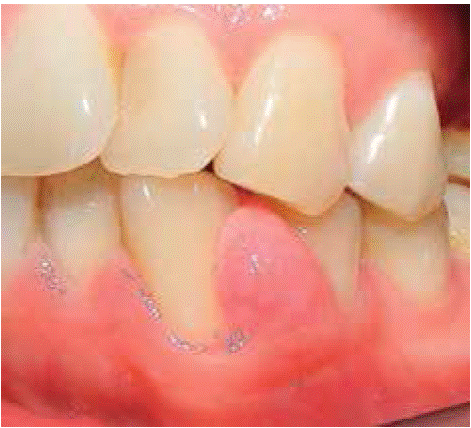

Clinical examination revealed an inflammatory gingival lesion around teeth 1.3 and 1.5, measuring 9 X 9 mm approximately and covering a third of the clinical crown. The lesion was asymptomatic, firm, lobulated, smooth and bleeding on stimulus (Figures 21and22).

Periodontal evaluation revealed presence of plaque and calculus, as well as a 50% oral hygiene index (O'Leary). Patient exhibited a caries lesion in the distal aspect of tooth 1.3.